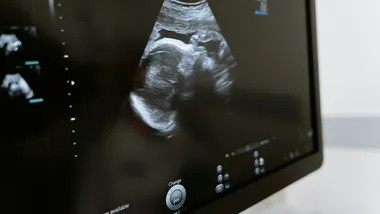

Війна та вагітність: як конфлікт впливає на здоров'я матерів

Дослідження показало критичні соціально-медичні наслідки воєнного конфлікту для вагітних жінок в Україні.

Вчені Львівського національного медичного університету імені Данила Галицького провели масштабне дослідження впливу воєнного конфлікту на вагітних жінок, яке розкриває глибокі соціально-медичні проблеми внутрішньо переміщених осіб.

Дослідження охопило 1000 вагітних жінок, розділених на три групи: переселенки з активних бойових дій, жінки, що переїхали з інших регіонів України під час конфлікту, та місцеві мешканки Львівської області. Мета дослідження — комплексно оцінити вплив воєнного конфлікту на медико-соціальні характеристики вагітних.